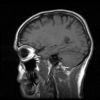

Hiedelem: Agyunknak csak 10 %-át használjuk.

Tény: Az orvosok és a humoristák előszeretettel emlegetik ezt a mondatot. Az idézetet időnként helytelenül Albert Einsteinnek tulajdonítják. Az MRI, PET és más képalkotó eljárások azonban azt mutatják, hogy az agynak nincsenek szunnyadó területei. Az egyes idegsejtek vizsgálata sem mutatott inaktív területeket. Az agysejtek vegyületeket előállító folyamatainak anyagcsere-vizsgálatai sem találtak olyan részeket, melyek nem működtek. A hiedelem valószínűleg a múlt század korai időszakából származik, amikor a különféle ügynökök arról próbálták meggyőzni az embereket, hogy még nem érték el a teljesítőképességük határát - állítja Carroll. Még azt a tényt sem veszi figyelembe, hogy a többi szervünk teljes hatásfokkal működik.